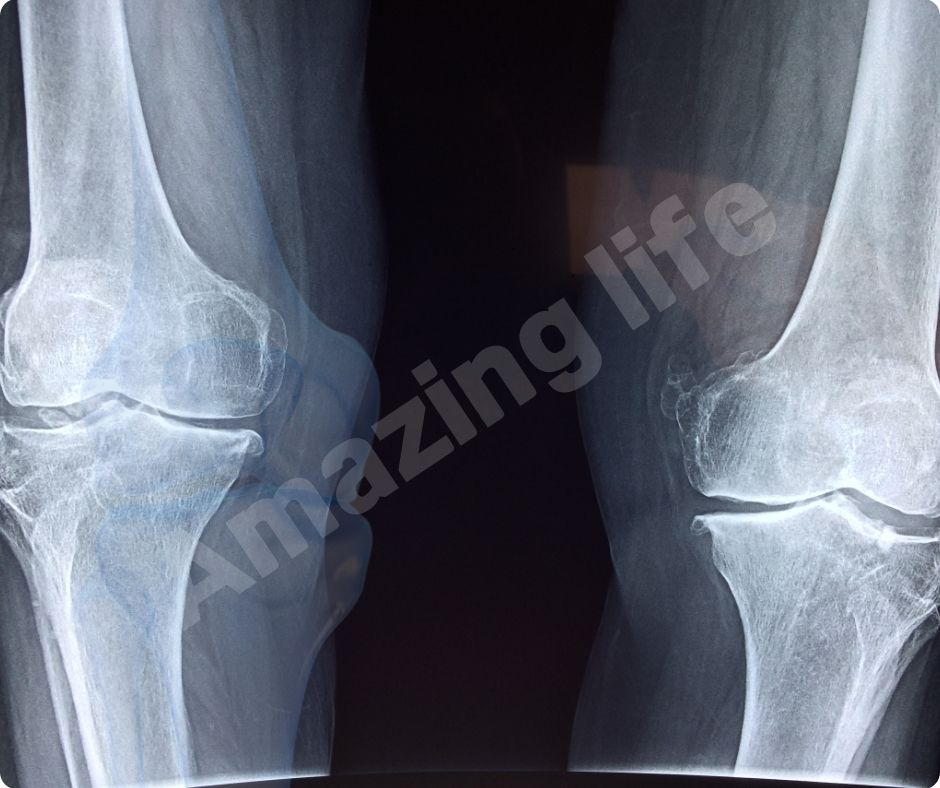

글루코사민은 신체 내에서 자연적으로 생성되며, 연골의 주요 구성 요소로 관절의 유연성과 기능을 유지하는 데 중요한 역할을 합니다. 특히 관절염과 같은 관절 문제를 예방하거나 완화하는 데 유용한 보충제로 많이 사용됩니다.

연골 보호 및 재생

글루코사민은 연골 조직의 구성 요소로서 연골의 손상을 막고 재생을 촉진합니다. 이는 특히 고령자나 관절에 많은 부담이 가는 운동을 하는 사람들에게 중요합니다. 글루코사민의 연골 보호 효과는 관절염의 진행을 늦추고 삶의 질을 향상시키는 데 큰 도움을 줍니다.